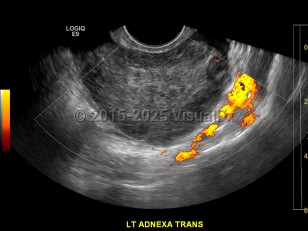

Ovarian torsion

Patients present in various manners, making this a challenge to diagnose in an emergency setting. The most classic presentation is a sudden onset of sharp / stabbing pain in either the right or left lower quadrant that only lasts a few seconds to a few minutes and then resolves to a dull ache, only to recur at various intervals with sharp / stabbing pains for a short amount of time. This presentation is associated more with partial or intermittent torsion. Patients also commonly present with a gradual onset of more colicky, unimpressive-type pain. Often patients will also complain of nausea / vomiting when pain occurs.

Risk factors include ovarian cyst with size greater than 4-6 cm or with solid components, history of prior torsion, pregnancy, and history of pelvic surgery. Patients may not have had a history of ovarian cysts prior.